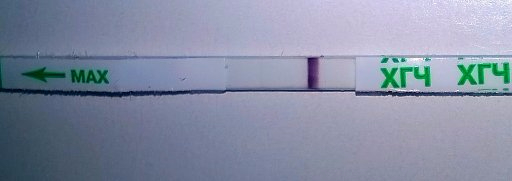

10-11дпо

Купила вчера тест мне неизвестный

Первый ответ Ева

вроде как он реагентит?

ну и видите что-нибудь?

даже не знаю что сказать.вроде есть,а вроде у тебя всегда такие тесты.не знаю,в замешательстве...

Вижу, но твоим только жирным поверю) уж прости